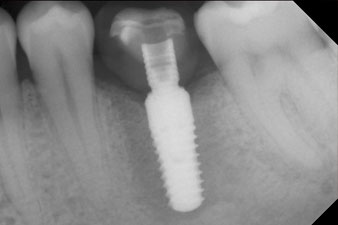

Fig. 1: Initial clinical situation after healing of extraction alveolus 36: The bone base is wide and there is sufficient keratinized gingiva.

Fig. 2: Six weeks later there was an incompletely ossified alveolus in the region of the mesial root.

Fig. 3: After preparation with the Implantmed implantology motor, an implant (diameter 4 mm, length 12 mm) was screwed in by the motor at a torque of 43 Ncm.